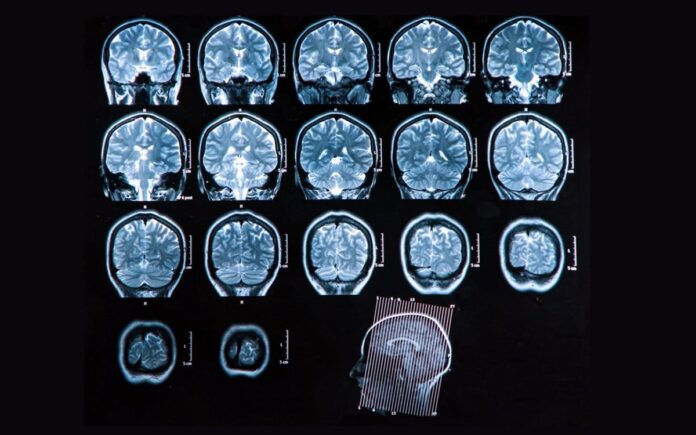

Η σκλήρυνση κατά πλάκας είναι μια αυτοάνοση νευροεκφυλιστική νόσος του κεντρικού νευρικού συστήματος, με την αιτιολογία της να μην είναι γνωστή όπως σε όλες τις αυτοάνοσες παθήσεις, με τον οργανισμό να επιτίθεται στον εαυτό του, αναγνωρίζοντας τα φυσιολογικά κύτταρα ως «εισβολείς».

Τουλάχιστον 2,3 εκατομμύρια άνθρωποι έχουν πολλαπλή σκλήρυνση παγκοσμίως. Τα περισσότερα άτομα με πολλαπλή σκλήρυνση διαγιγνώσκονται μεταξύ των ηλικιών 25 και 40, με περίπου δύο φορές περισσότερες γυναίκες από τους άνδρες.

Η αιτία της πολλαπλής σκλήρυνσης δεν είναι ακόμη γνωστή και μέχρι στιγμής δεν υπάρχει οριστική θεραπεία, αν και υπάρχουν διαθέσιμες θεραπείες που μπορούν να επιβραδύνουν ορισμένες μορφές και υπάρχουν πολλές επιλογές για τη βελτίωση και τη διαχείριση των συμπτωμάτων.